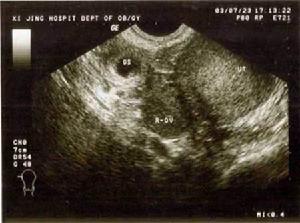

(三)超声诊断 早期输卵管妊娠时B超显象可见子宫增大,但宫腔空虚,宫旁有一低回声区此种图象并非输卵管妊娠的声象特征,需排除早期宫内妊娠伴有妊娠黄体的可能。用超声检测妊娠囊和胎心搏动对诊断异位妊娠十分重要如妊娠位于宫外,即可诊断为宫外妊娠;妊娠囊位于宫内,则多可排除宫外妊娠B超早期诊断间质部妊娠有重要临床意义,可显示一侧子宫角突出,局部肌层增厚内有明显的妊娠囊。